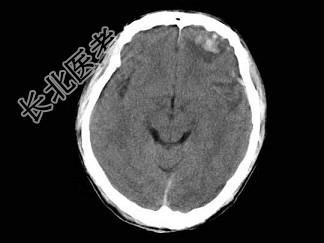

- 单项选择题成人,外伤后1小时, CT检查如图,最可能的诊断为 ( )

A、脑出血

B、脑膜瘤

C、脑转移瘤

D、脑挫裂伤

E、钙化灶